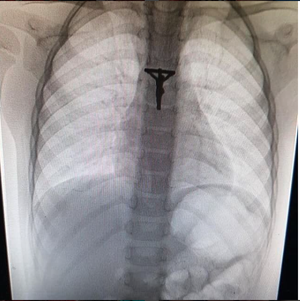

Foreign body in a 3 year old boy

The X-ray gives the impression Jesus is in his heart.